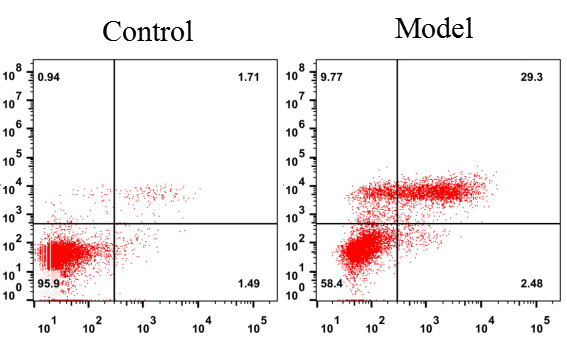

2.2流式检测肺泡灌洗液嗜中性粒细胞比例(Gr-1、CD11b双标)